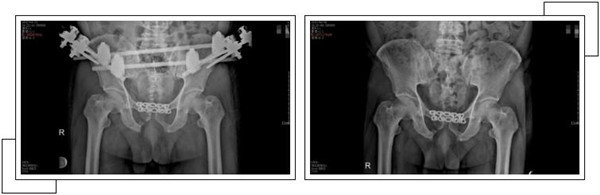

二周后,趙大叔病情穩(wěn)定,身體各方面條件符合手術(shù)指征后,骨科中心副主任羅軍帶領(lǐng)手術(shù)團(tuán)隊(duì)為其進(jìn)行了骨盆骨折、恥骨聯(lián)合分離、雙側(cè)髂骨骨折、右側(cè)恥骨上下支骨折切開復(fù)位內(nèi)外固定術(shù),手術(shù)一個半小時順利完成。

經(jīng)過關(guān)節(jié)科全體醫(yī)護(hù)人員的精心治療和護(hù)理,術(shù)后一個月,趙大叔康復(fù)出院。出院當(dāng)天,趙大叔感謝的話說了又說,并在來復(fù)查時,特地制作了一面錦旗以表示謝意。